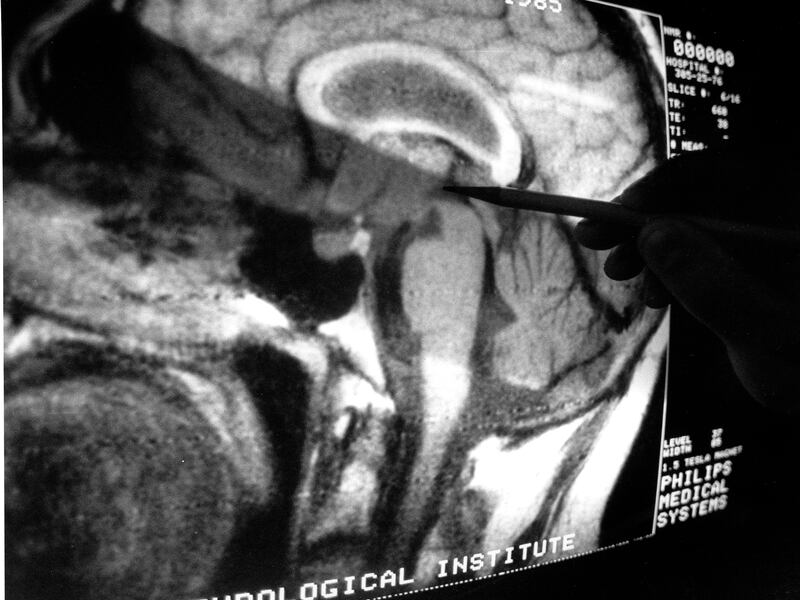

MRI scans: The main study noted that data from MRI scans is far more accurate than other methods of assessing mental illness, such as questionnaires. The best way to get accurate data is through an MRI, which isn’t always accessible.

- One problem with performing MRI scans is the cost. MRIs can add up to a total of around $1,000 an hour, which can stand in the way of using larger sample sizes, the study stated.